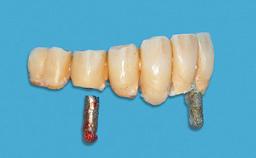

Four Immediately Loaded Mini-Implants Supporting a Mandibular Overdenture

# of Implants 4

Type of Implants One-Piece|Reduced-Diameter

Defining Characteristics Fully edentulous lower jaw to be rehabilitated with an implant-borne removable overdenture